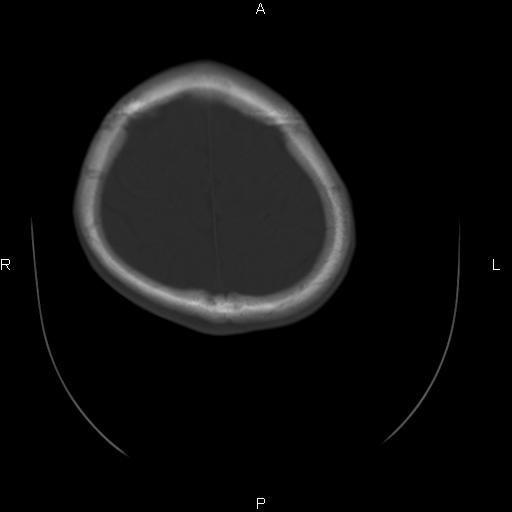

标题: CT27115:大家看一看,这孩子的颅骨表现? [打印本页]

标题: CT27115:大家看一看,这孩子的颅骨表现?

两名中学生打架,脑质内未见异常,未上传。

两例——颅骨结构正常,未见明显骨折征象。

感觉第2个颅缝密度高,额顶部板障有点厚,正常变异?地中海贫血?